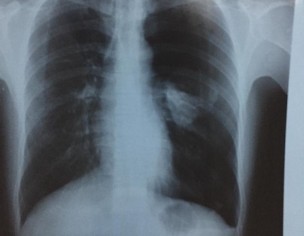

I have Pain in Left side Chest. My ECG report and Chest X Ray is attached. Kindly advice me what actual problem

x ray showing left sided opacity,should be investigated,unable to comment without examining patient.

your Chest Xray has left sided opacity. you need to be checked by pulmonologist who may advise further investigations in order to reach the diagnosis.